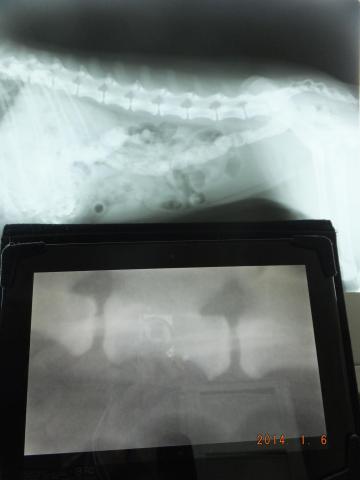

上が生のレントゲン写真で、下にKALOSを置いています。

同程度の拡大率で表示しているのですが、この時点だと、生のレントゲン写真のほうが広範囲が見られるので、いいように思えます。しかし、